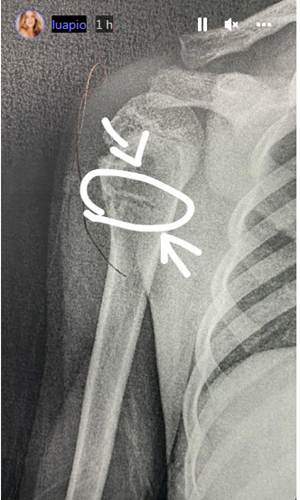

Em vÃdeo, Piovani fala do drama de Dom e ainda é possÃvel ouvir Liz, de seis anos, gêmea de Bem, perguntando sobre o pai, Pedro Scooby. “Domzuco fraturou o ombro, pela primeira vez que Deus me ajude que sejam pouquÃssimas, que isso não se repita.

Mas agora está aqui tomando Novalgina, gelo, semana que vem volta, e agora tenho que cuidar dos gêmeos, e ser babá dele”, desabafou Luana, que também mostrou a radiografia da fratura.